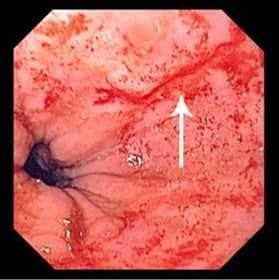

- Эзофагогастроскопия. Введение гибкого эндоскопа через ротовую полость позволяет оценить состояние эпителиальной оболочки верхних отделов ЖКТ и обнаружить линейные разрывы, которые обычно локализованы в области перехода пищевода в желудок. С помощью визуального осмотра удается установить глубину поражения стенки пищевода или желудка.

Для диагностики описываемого синдрома в первую очередь применяют эндоскопическое исследование (эзофагогастроскопию). Данное обследование дает возможность четко увидеть локализацию и глубину дефекта стенки органа.

Окончательный диагноз Синдром Мэллори-Вейса ставится во время проведения ЭГДС. Как правило кровотечение останавливается самостоятельно за 24—48 часов. Иногда требуется эндоскопическое лечение. Открытое вмешательство выполняется при тяжелой степени кровопотери и безуспешности эндоскопического гемостаза, выраженных анатомических поражениях кардиального жома.